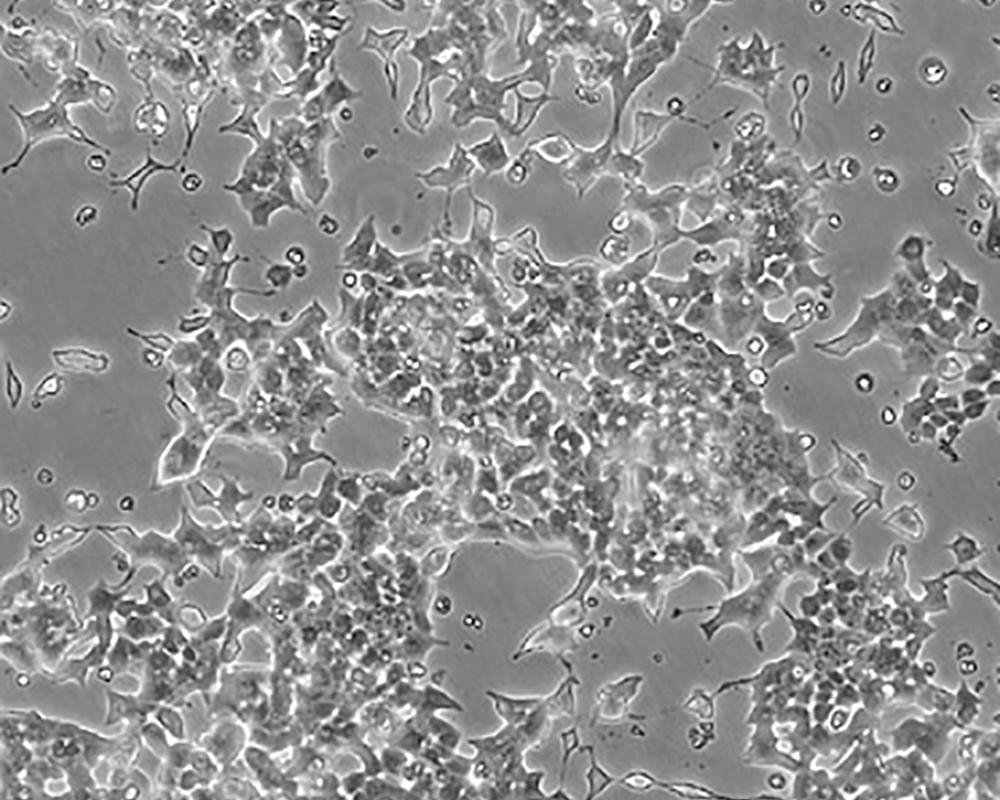

Beta-TC-6

產(chǎn)品名稱 Beta-TC-6

中文名稱 小鼠胰島素瘤胰島β細胞

組織來源 胰島素瘤

生長特性 adherent

形態(tài)特征 epithelial

細胞描述 這株細胞來源于轉(zhuǎn)基因小鼠中生長的一個胰腫瘤(胰島素瘤)。這種小鼠攜帶了大鼠胰島素II基因啟動子調(diào)控的SV40早期基因的假基因結(jié)構。細胞包含豐富的胰島素和小量的胰高血糖素及生長抑素。響應葡萄糖而分泌胰島素